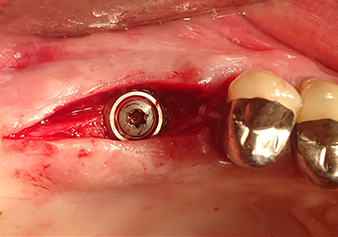

Situation après l’insertion de l'implant

Fig.9 : Situation après l’insertion de l'implant (longueur : 10 mm, plateforme prothétique : 6,5 mm) juste avant de suturer.